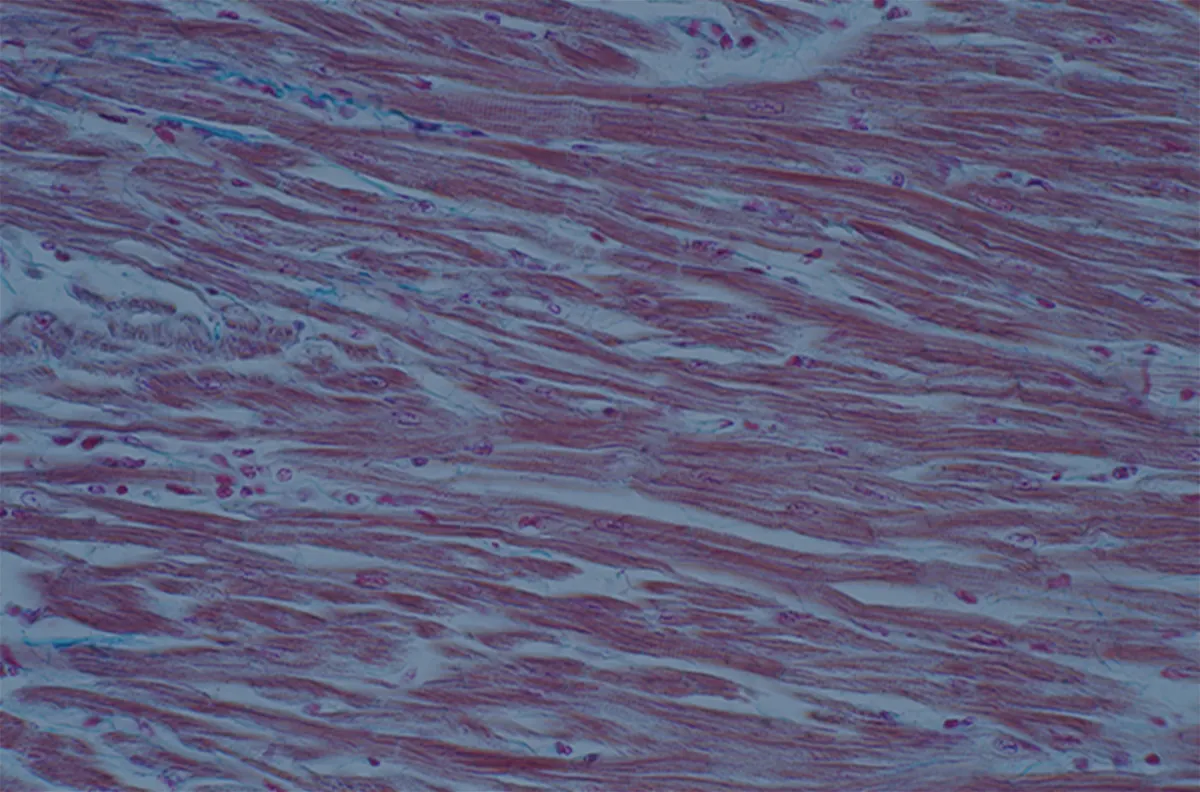

皮膚の弾力成分の減少